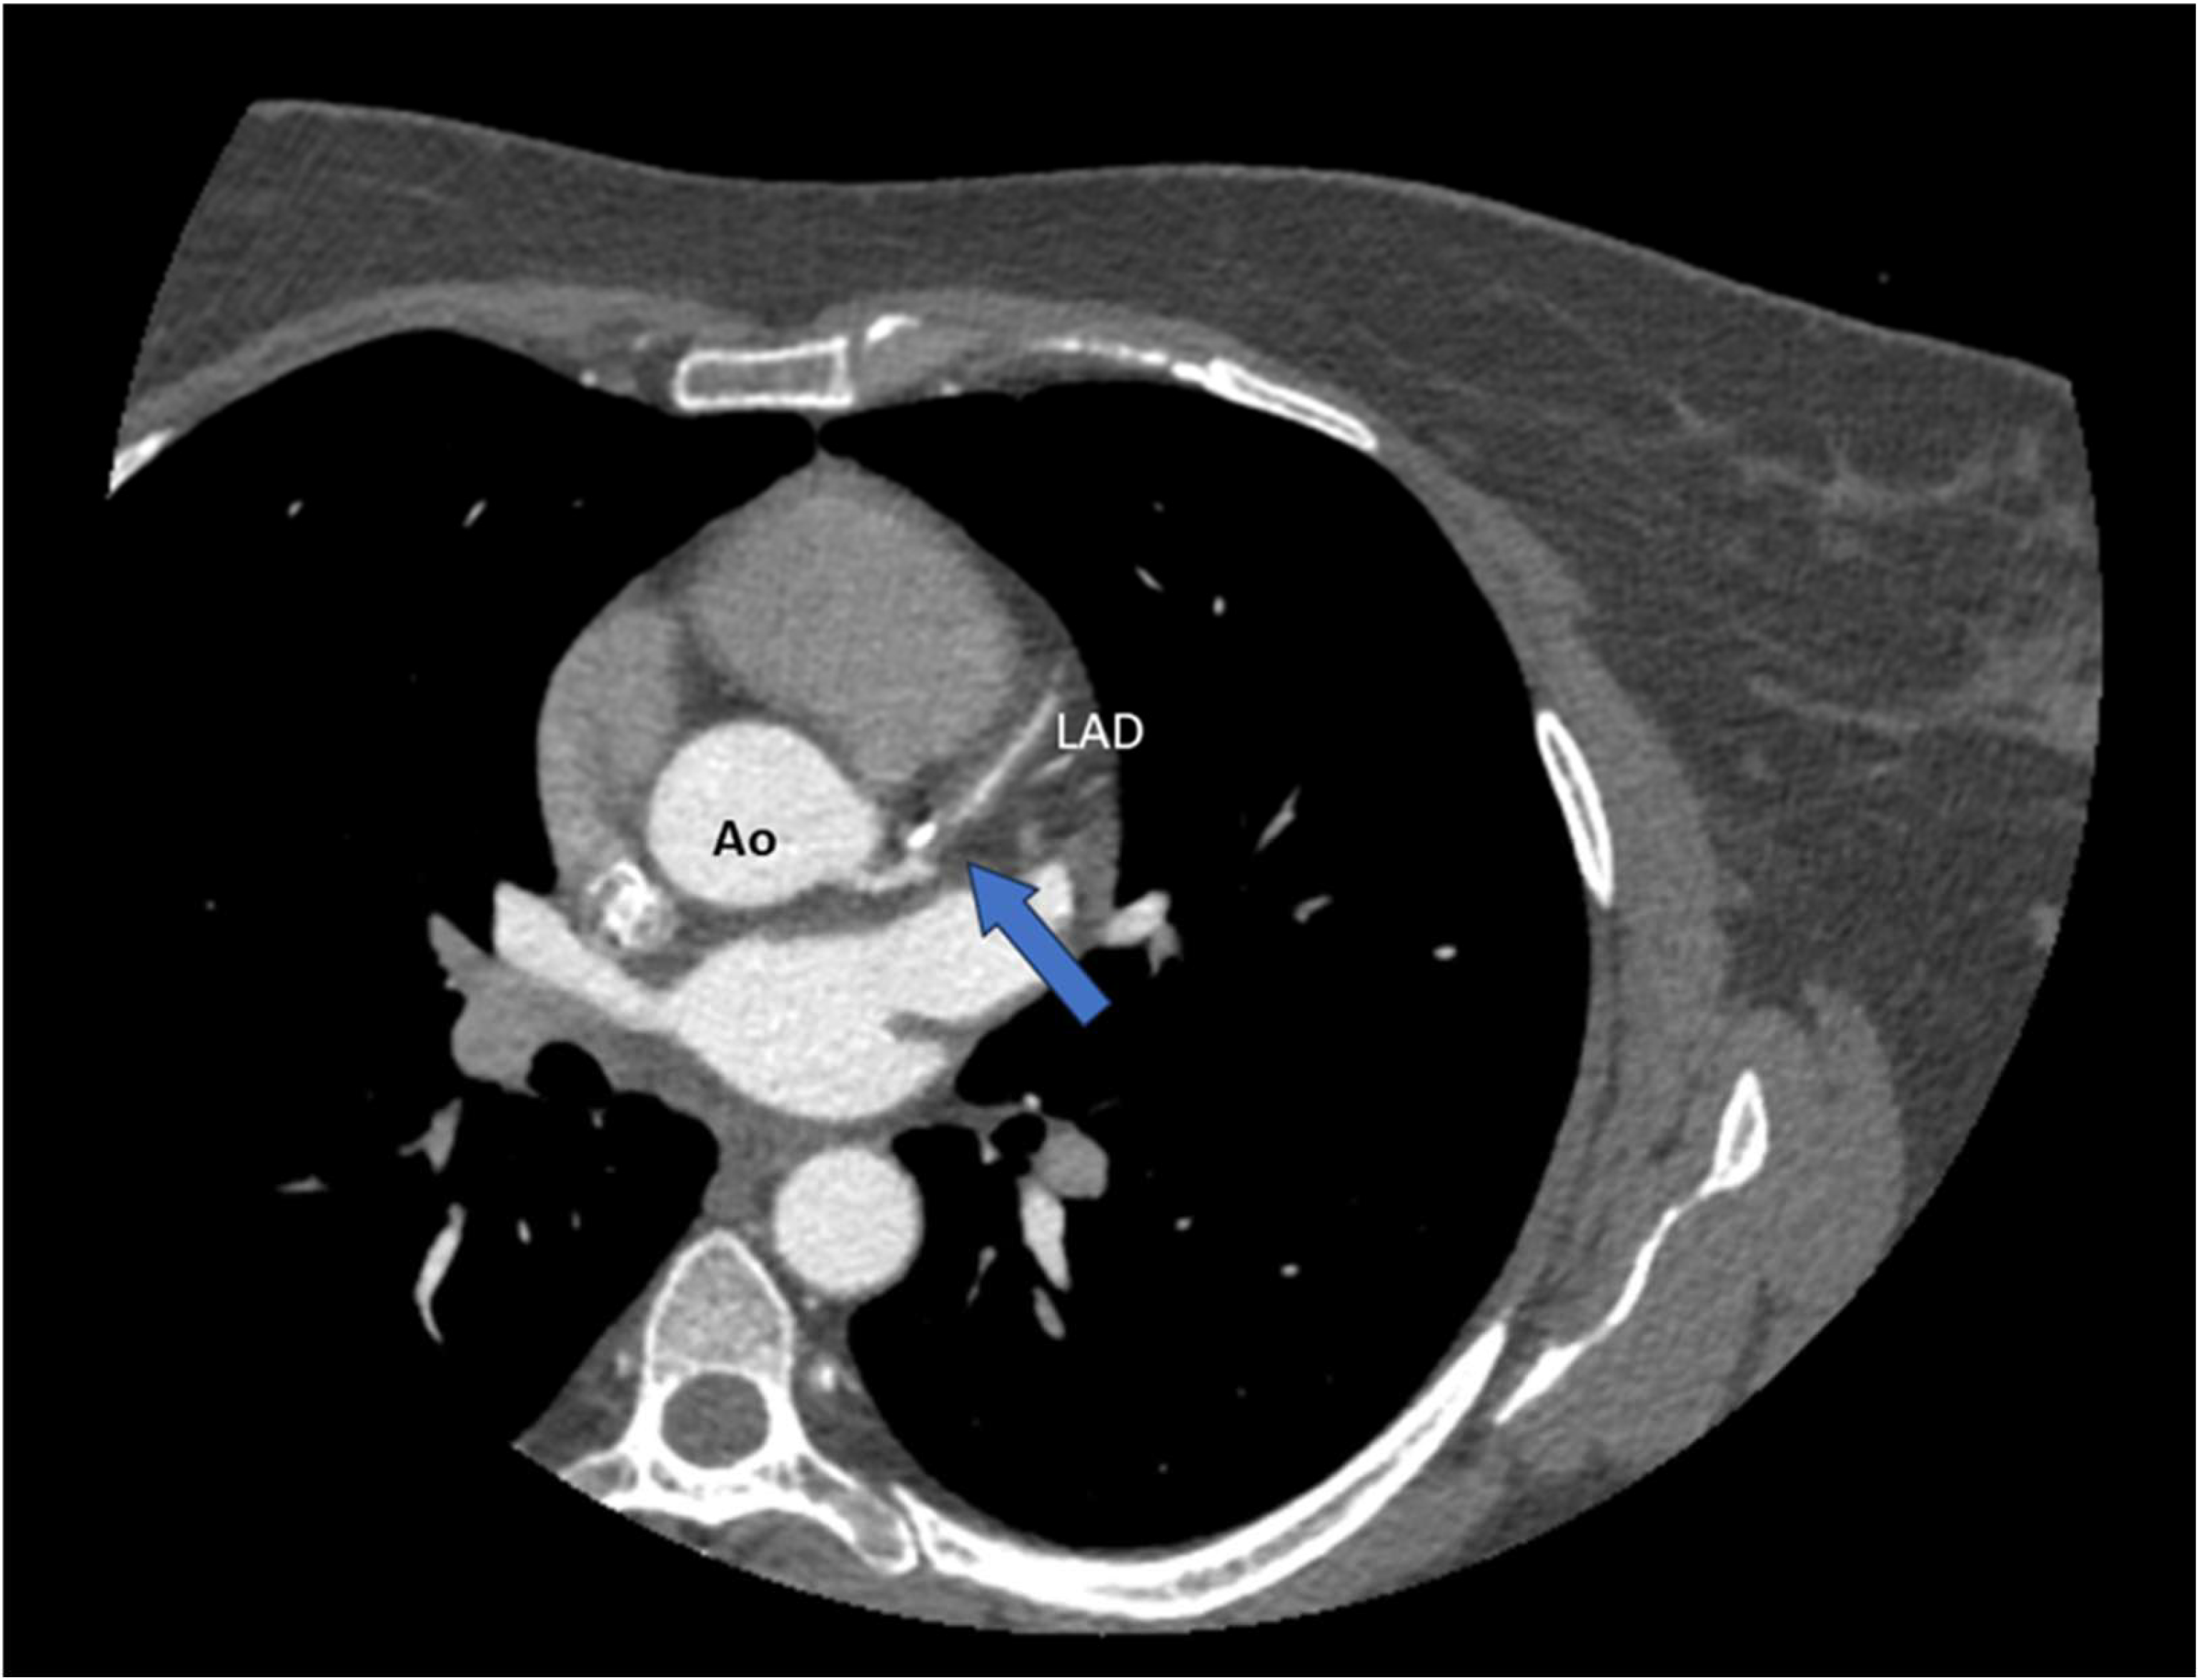

4.2. Non-Invasive Imaging Methods in SCAD

4.2.1. CT Coronary Angiography